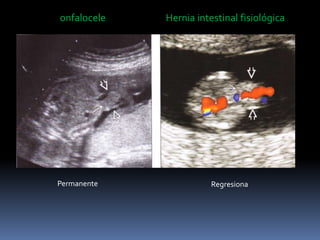

onfalocele Hernia intestinal fisiológica

Permanente Regresiona